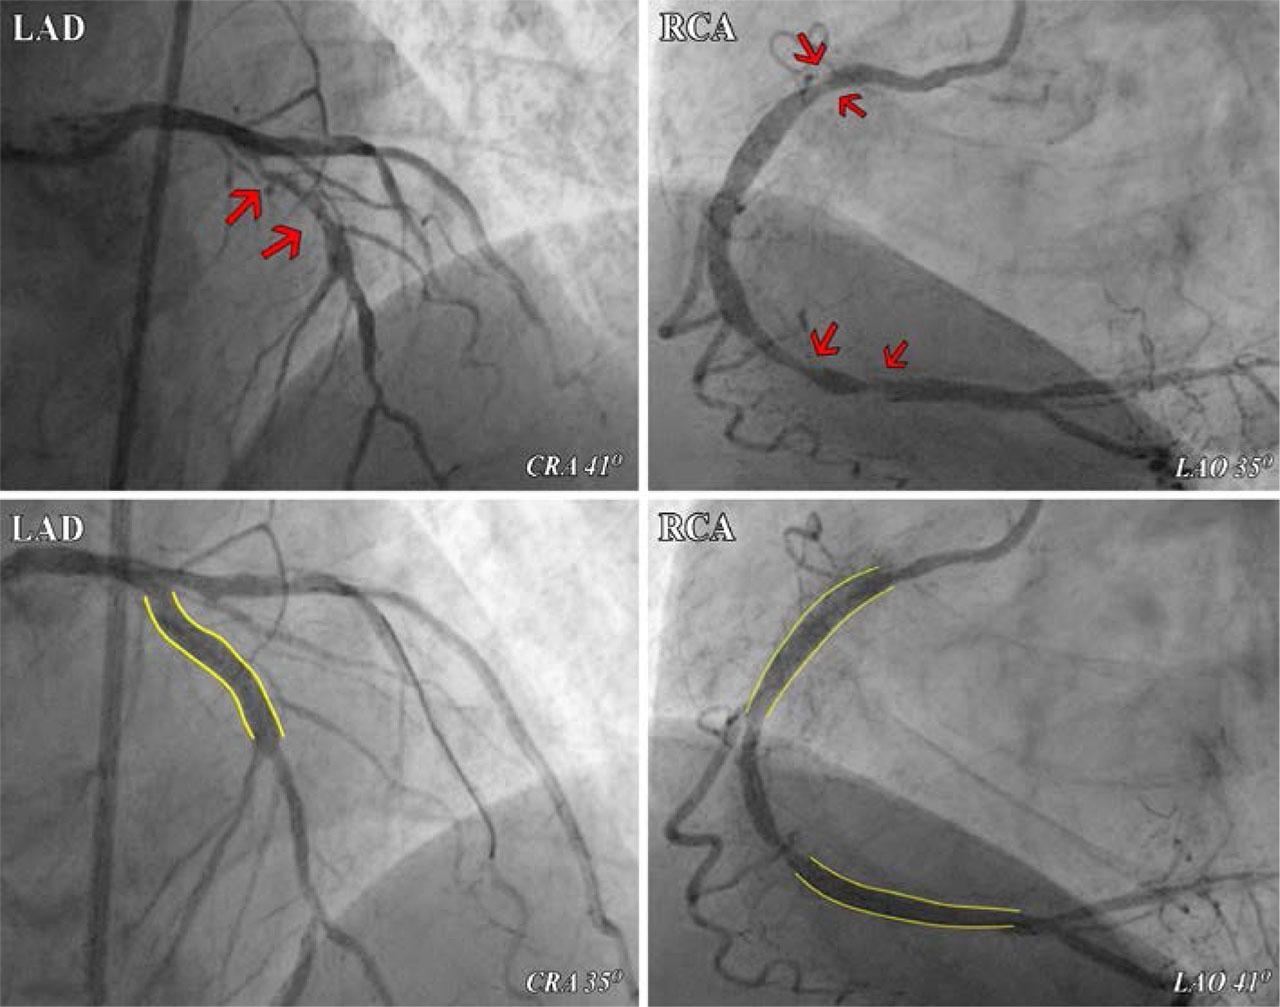

Following the CCTA identification of calcium distribution in the coronary arteries, revascularization started with the heavily calcified LAD, first preparing the lesion using a cutting balloon. After successful lesion preparation, a drug-eluting stent was implanted with TIMI3 postprocedural flow. In the next step, two drug-eluting stents were implanted in the RCA (Figure 4). The clinical evolution was favorable, without any complications, and the patient was discharged on double antiplatelet therapy, high-dose statin, ACE inhibitor and beta-blocker. At the 1-month follow-up, the patient was free of events, with minimal loss in ejection fraction and reduction of LDL-C below the target level for high-risk patients (45 mg/dL).

Coronary angiography showing severe vascular disease. Red arrows, coronary stenoses on LAD and RCA; yellow lines, sites of stent implantation with minimal residual stenoses